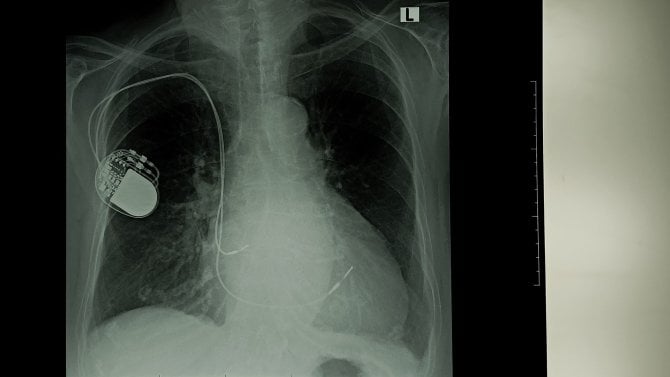

Kardiostimulátor je malé přístrojové zařízení, které slouží k terapii pacientů s poruchami srdečního rytmu. Díky moderní medicíně dnes umožňuje lidem s arytmiemi žít plnohodnotný a aktivní život. Implantace je běžný zákrok a současné přístroje jsou velmi spolehlivé.

Kardiostimulátor se používá především u pacientů, jejichž srdce bije příliš pomalu nebo nepravidelně. Přístroj vysílá jemné elektrické impulzy, které podporují správnou činnost srdečního svalu. Nejčastěji se zavádí pod kůži v oblasti pod klíční kostí a propojuje se elektrodami se srdcem.